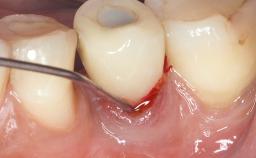

A 72-year-old female patient was referred to the specialist clinic with signs of peri-implantitis associated with implant 14. Two implants (sites 14 and 15) had been in function for three years. The patient was in good general health and was not taking any medication. She was a former smoker (12–15 cigarettes a day for 50 years) but had ceased smoking two years prior to implant placement. Her periodontal condition was stable, with no probing depths above 5 mm and a full-mouth plaque score (FMPS) of 35%.